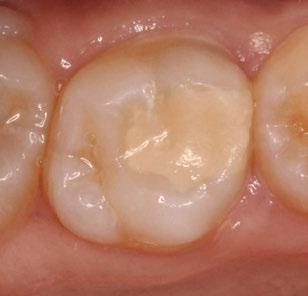

La exploración intraoral (figuras 4 a 8) revela una Clase II molar y canina completa, líneas 1/2 dentarias superior 0,5 mm e inferior 1 mm ambas desviadas hacia la derecha, los incisivos superiores excesivamente protruidos y vestibulizados (seguramente debido a la interposición del labio inferior), resalte de 13 mm y sobremordida 2/3 de corona. La discrepancia oseodentaria

inferior es de -3,5 mm y la curva de Spee de 4 mm.